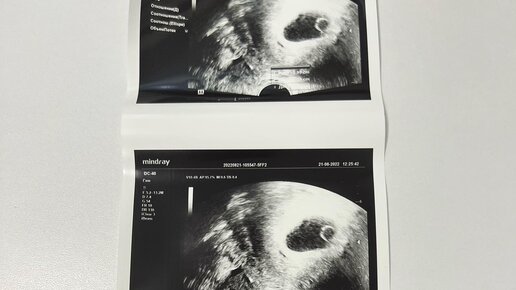

Есть беременность, 8 недель, есть плодное яйцо 3,4 см, а эмбриона внутри его нет.  Есть желточный мешочек. А эмбриона нет.   Это значит, что мне надо делать срочно делать аборт…  Это называется анэмбриония. Я раньше не знала, что так бывает, но это случилось со мной.   Все подтвердилось вчера. Я пишу и плачу.   Это разновидность замершей беременности.   21 авг я сделала узи в платной клинике, в которой я наблюдалась. Там была картина такая же как вчера, но мы надеялись, что эмбрион «проявится». Я сделала два анализа ХГЧ, 21 и 25, - последний показал снижение на 10000, но мы все ещё надеялись...